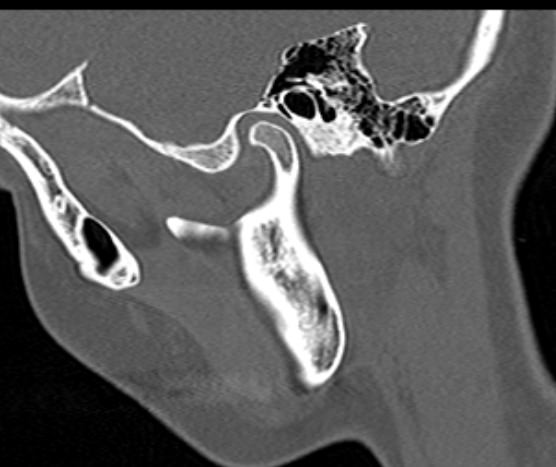

Наиболее точным и информативным методом диагностики костной патологии ВНЧС является мультиспиральная компьютерная томография. КТ относится к лучевым методам исследования, то есть для сканирования применяется рентгеновское излучение. В отличие от обычного рентгена томограф проводит одномоментно множество тончайших срезов исследуемой зоны, которые в дальнейшем проходят цифровую обработку. В результате получаются детальные снимки и трехмерные изображения области височно-нижнечелюстных суставов, которые позволяют проводить точную и достоверную диагностику.

Для оценки функции височно-нижнечелюстных суставов КТ-сканирование проводится в нескольких положениях: с открытым ртом и закрытым ртом. С помощью таких функциональных проб можно оценить положение суставной головки нижней челюсти при движениях нижней челюсти, выявить привычные вывихи и подвывихи суставов.

Компьютерная томография позволяет оценить состояние костных структур височно-нижнечелюстных суставов, так как рентгеновские лучи хорошо задерживаются костной тканью. Для повышения диагностических возможностей компьютерной томографии в ряде случаев дополнительно проводится контрастное усиление путем внутривенного введения йодсодержащего контрастного препарата. Эта методика применяется для улучшения визуализации мягких тканей, которые хуже видны при нативном исследовании.

С помощью КТ можно оценить состояние костной ткани суставных головок нижней челюсти, внутрисуставного мениска, суставной капсулы, связочного аппарата и жевательных мышц.